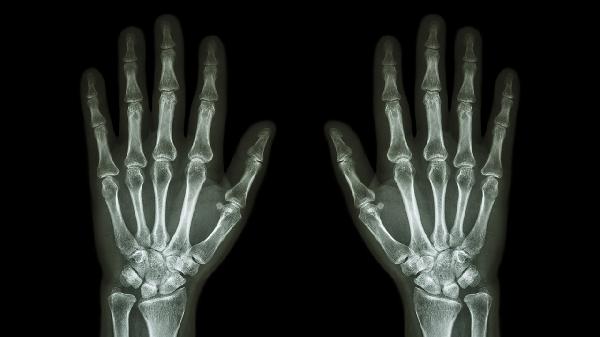

手指撞击或扭伤可能导致关节周围韧带、肌腱损伤,表现为局部肿胀、压痛和活动受限。轻微损伤可通过冰敷缓解肿胀,48小时后热敷促进血液循环。若伴随关节畸形或持续疼痛,需排除骨折可能,必要时拍摄X线片。